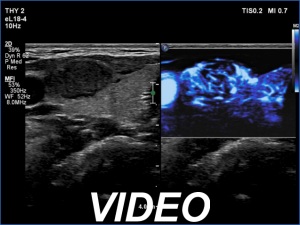

Ultrasonography. The thyroid was echonormal and presented two discrete lesions in the right lobe. The larger, upper one showed irregular margins, abutting and bulging contours and had back wall figures. The intranodular vascularization was significantly increased. The smaller lesion had microcalcifications and presented taller-than-wide shape.

Comment. It is worth thoroughly analyzing the intranodular echogenic figures. These are partly linear and most of them are related to tiny ventral cystic areas.